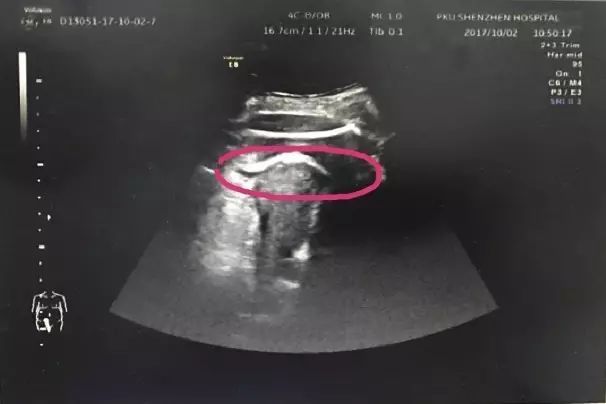

gif_animation 海外の病院で、母親のお腹の中にいる胎児が強力な蹴りで子宮壁を突き破り、緊急の帝王切開が行われたとの事。その後、母親と赤ちゃんは無事。その凄まじさから ”史上最強の赤ちゃん” なのではないかという声も。画像2枚。(※ TOP画はイメージ)